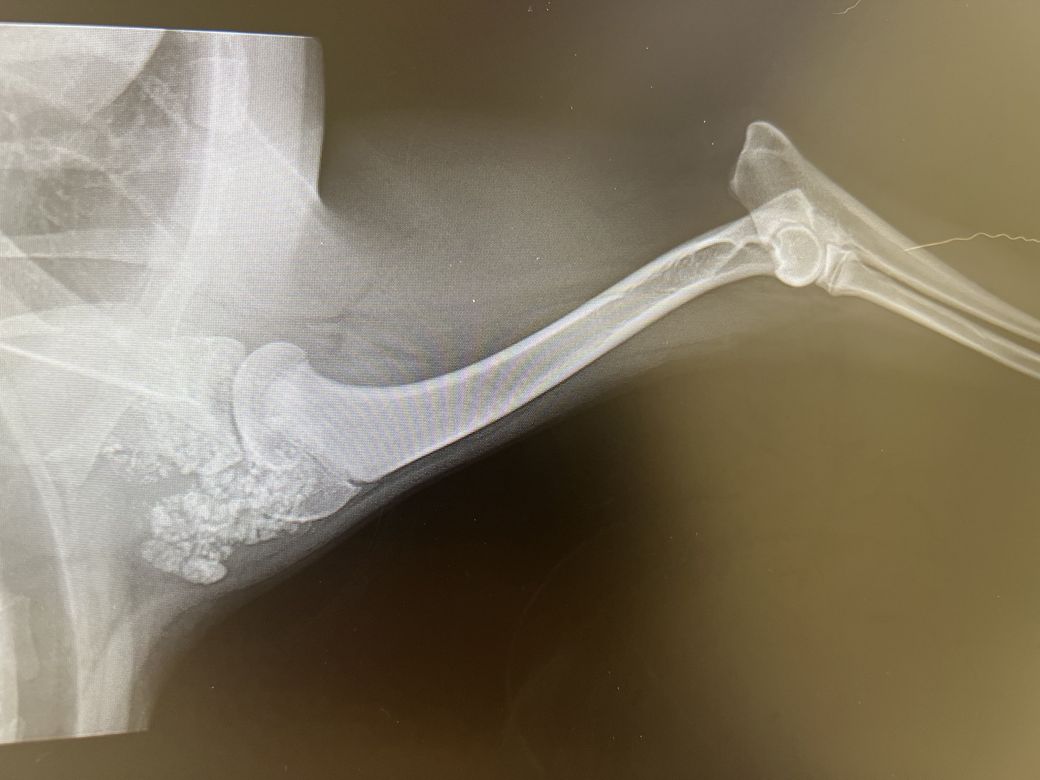

사진을 옆으로 보셔야 합니다

아랫 사진이 파행 다리입니다 위에 사진은 오른 다리구요

물론 첨부해주신 사진 중 아래 사진을 보면

상완골의 수질부 밀도가 근위 metaphysis부근, 원위부 영양공의 근위 부분으로 부분적인 증가 양상을 보이고 있어 범골염 가능성도 같이 보이고 있습니다.

하지만 원본 사진을 보지 않은 상태에서는 추정일 뿐입니다.